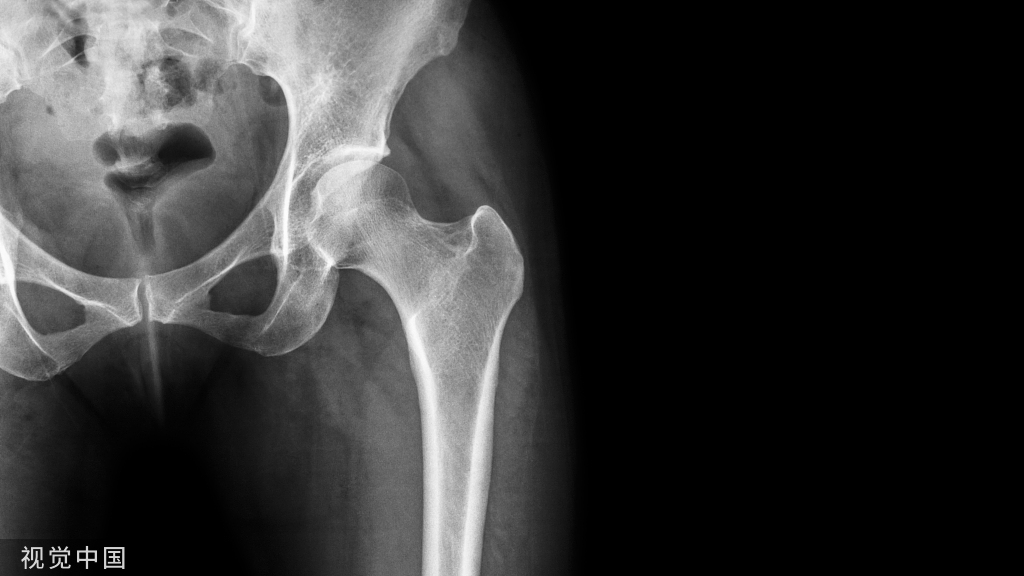

髋关节复位后的固定、功能锻炼技巧!

复位后并不意味着治疗已经结束了,复位后的固定以及功能锻炼非常关键,复位后用抬腿垫将髋关节固定于轻度外展位,复位后六周内禁止髋关节内旋、内收、髋关节屈曲大于90°。